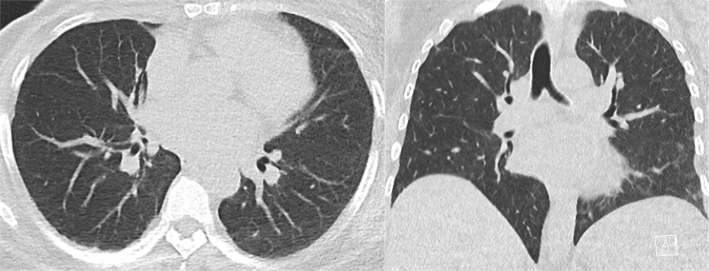

Case report: We report the case of a 46-year-old female with metastatic HER2-mutated breast cancer who had received multiple lines of HER2-targeted therapies. The patient presented with suspected lung and mediastinal lymph node progression, despite a good response at other affected sites. A lymph node biopsy revealed non-necrotizing pulmonary granulomas, with negative microbiological testing. Further evaluations showed highly elevated anti-PR3 autoantibodies, while angiotensin-converting enzyme (ACE) and calcium levels remained within the normal range. Pulmonary function tests confirmed a restrictive syndrome. Nasal fibroscopy identified chronic sinusitis with massive nasal polyposis, without renal or cutaneous involvement. High-dose corticosteroid therapy was initiated, leading to a favourable response. Based on the clinical presentation, radiological findings, and pathological features, we concluded that the granulomatosis was related to HER2-targeted therapy.